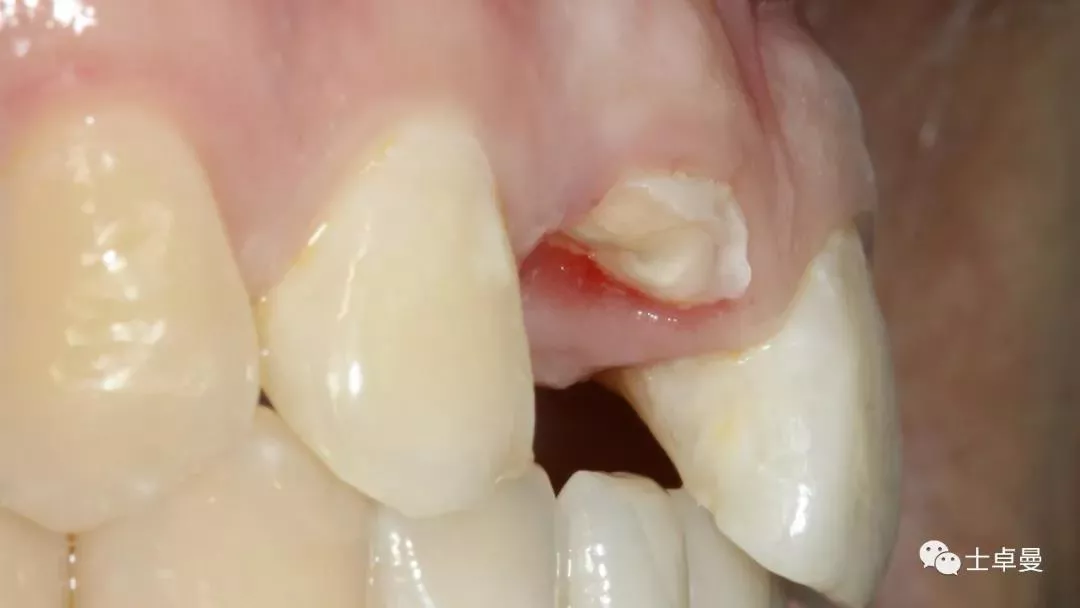

保留唇侧牙片

牙周探针探查牙片位置及松动度

就位种植外科导板

指示杆观察备孔三维位置

种植体植入后,植体唇侧间隙内填塞骨粉0.25g,胶原骨100mg,安放愈合帽,明胶海绵暂时封闭创面